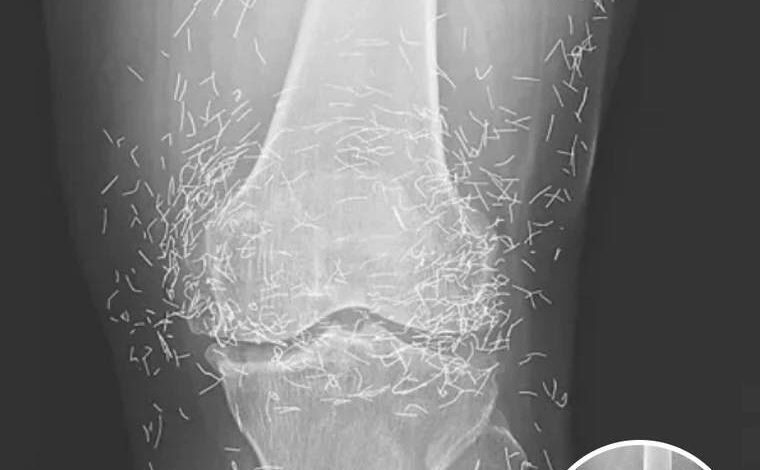

When a 65-year-old woman walked into a medical clinic in South Korea complaining of chronic, debilitating joint pain, the physicians expected to see the standard markers of a long-term degenerative condition. They anticipated the narrowing of joint spaces, the telltale bone spurs, and the loss of cartilage that defines a life lived with osteoarthritis. However, the moment the X-ray film was developed, the medical team was met with a sight that defied conventional clinical experience. Staring back at them from the glowing screen were hundreds of tiny, hair-thin gold needles, meticulously embedded deep within the soft tissue and muscle surrounding her knees. This was not a sudden injury or a freak accident; it was the physical map of a years-long battle against pain that had pushed a patient to seek an extreme form of alternative relief.

Desperate for a solution that didn’t involve a chemical trade-off, she turned to the deep-rooted traditions of her culture. In many parts of Asia, particularly South Korea, acupuncture is not just a secondary option; it is a primary pillar of the healthcare system. However, the specific procedure she underwent went far beyond the typical temporary insertion of needles. In a practice known as gold thread or needle implantation, practitioners intentionally leave the needles inside the body. The theory behind this controversial method is that the gold provides continuous, long-term stimulation to the acupuncture points, theoretically offering a permanent blockade against the pain signals caused by arthritis. To the patient, it was a promise of a life without pills; to the doctors who saw the X-ray decades later, it was a potential medical time bomb.

Beyond the biological risks, these hidden needles pose a significant challenge to modern diagnostic technology. In the field of radiology, metal is a notorious disruptor. These hundreds of gold fragments create “artifacts” on imaging, appearing as bright white streaks that can obscure the very anatomy doctors need to see. This makes it incredibly difficult to track the progression of the patient’s arthritis or to screen for other underlying issues like bone tumors or fractures. The presence of metal also creates a dangerous barrier to one of the most powerful tools in medicine: the MRI. Because an MRI uses incredibly strong magnets, any metallic object inside the body can be subjected to intense force. If a patient with gold needles were to accidentally undergo an MRI, the magnetic pull could cause those needles to migrate through the tissue, potentially puncturing nerves, slicing through tendons, or tearing open major blood vessels, leading to life-threatening internal bleeding.

The woman’s case, which was eventually documented in the prestigious New England Journal of Medicine, has become a landmark cautionary tale for healthcare providers and patients alike. It highlights the profound disconnect that can sometimes exist between traditional beliefs and modern safety standards. While the woman may have felt an initial sense of relief from the “continuous stimulation” of the gold, she was ultimately left with a knee joint that was a literal minefield of metal. The X-rays serve as a haunting visual reminder that our bodies are not meant to be permanent containers for external materials, no matter how precious the metal may be.